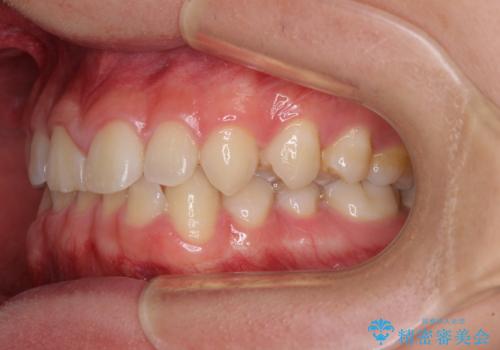

隙間とデコボコを治したい ワイヤー装置による矯正治療

- 前歯のデコボコと隙間を気にして来院された患者様です。

治療手段としてはワイヤー装置でもインビザラインでも可能でしたが、インビザラインの自己管理は自信がないとのことで、ワイヤー矯正により隙間を閉じていくこととしました。

隙間の原因は舌の突出癖であったので、舌癖改善のためのトレーニングを指導しながら治療を進めて行くこととしました。

舌の突出癖がなかなか改善されず、治療開始時よりも隙間が大きく開いてしまう時期がありましたが、最終的にしっかりと閉じて終了することができました。